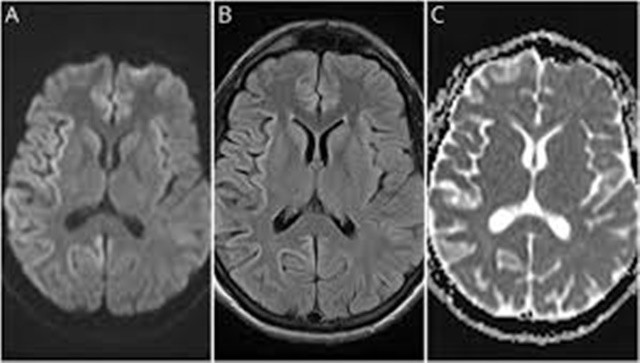

CJD là một chứng rối loạn não nghiêm trọng do các protein gọi là prion gấp sai và tạo thành các lỗ trên não. Điều này làm gián đoạn sự giao tiếp giữa các tế bào và dẫn đến chứng mất trí nhớ cũng như các triệu chứng như mất trí nhớ, khó nói, vấn đề về thăng bằng và cử động giật cục. Khoảng 85% trường hợp không rõ nguyên nhân, phần lớn những trường hợp còn lại là do đột biến gen của protein prion. Ít hơn 1% được tìm thấy ở những bệnh nhân ăn thịt từ động vật mắc bệnh bò điên, được biết đến trên lâm sàng là bệnh não xốp dạng bò (BSE).